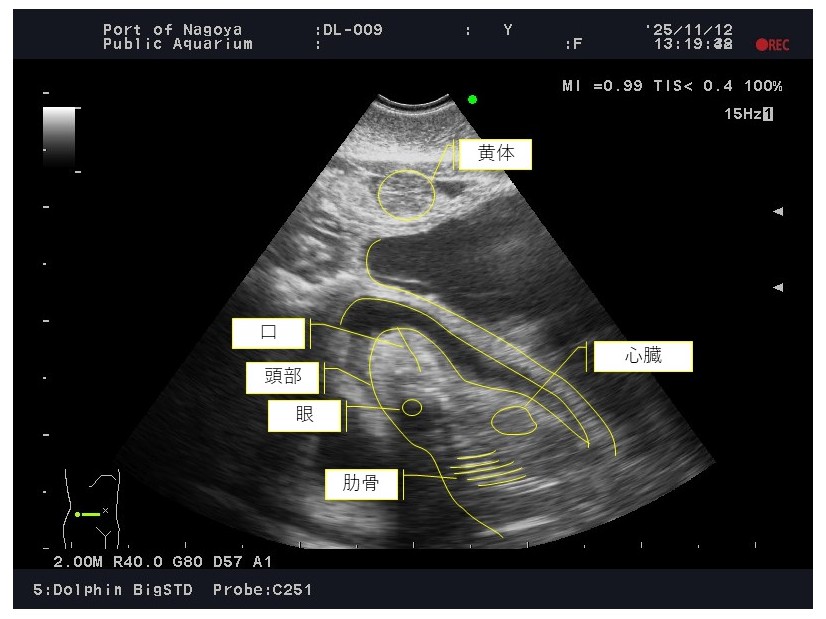

4 ベルーガ「ナナ」の超音波(エコー)画像 (令和7年11月12日撮影)

胎仔が動く様子も確認しています